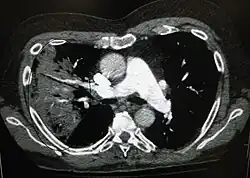

Pro stanovení diagnózy se často používá rentgenový snímek hrudníku.[10] U osob s mírnými projevy onemocnění je snímkování potřebné pouze u osob s potenciálními komplikacemi, u pacientů, jejichž stav se ani při léčbě nelepší, nebo u těch, u nichž je příčina onemocnění nejasná.[10][37] Pokud je stav nemocného natolik vážný, že je nezbytná hospitalizace, doporučuje se provést rentgen hrudníku.[37] Nález však ne vždy odpovídá závažnosti onemocnění a ne vždy spolehlivě rozliší mezi bakteriální a virovou infekcí.[10]

Rentgenové snímky zápalu plic lze klasifikovat jako lobární pneumonii, bronchopneumonii (rovněž známou jako lalůčkový zápal plic) a intersticiální pneumonii.[40] Bakteriální, komunitně získaná pneumonie klasicky vykazuje známky plicní konsolidace jednoho segmentálního plicního laloku, tedy znaky lobární pneumonie.[20] Nálezy se však mohou lišit, a u dalších typů zápalu plic jsou běžné jiné charakteristiky.[20] Aspirační pneumonie může vykazovat oboustranné zastínění zejména ve spodní části plic a na pravé straně.[20] Rentgenové snímky virového zápalu plic se mohou jevit normální, vykazovat hyperinflaci, ostrůvkovité oblasti konsolidace plicní tkáně na obou plicích nebo se podobat bakteriálnímu zápalu plic s lobární konsolidací.[20] V raných fázích onemocnění nemusí být radiologické nálezy patrné, zvláště při dehydrataci, nebo může být obtížné je interpretovat u obézních osob nebo těch, kteří již onemocnění plic prodělali.[11] Počítačová tomografie může u nejasných příčin poskytnout další informace.[20]

Ve vzácných případech vytvoří bakterie v plíci dutinu naplněnou infikovanou tekutinou zvanou plicní absces.[74] Plicní abscesy jsou obvykle viditelné na rentgenovém snímku hrudníku, pro potvrzení diagnózy je ale často zapotřebí CT snímek hrudníku.[74] Abscesy se typicky objevují při aspirační pneumonii a často obsahují několik typů bakterií. Plicní absces se obvykle léčí dlouhodobě podávanými antibiotiky, někdy ale musí být absces vyprázdněn chirurgem nebo radiologem.[74]